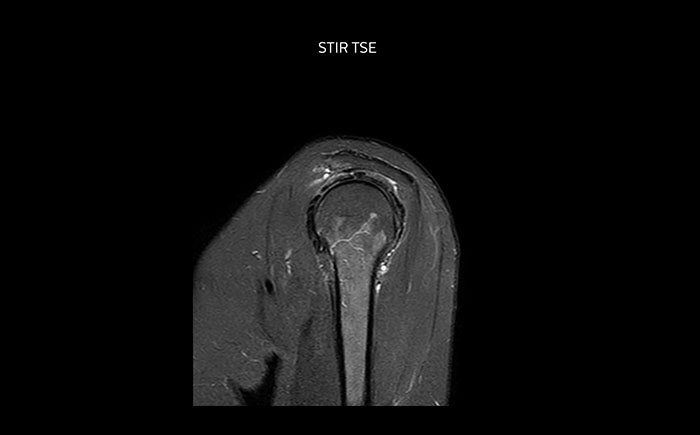

The Prodiva shoulder coil is very flexible and has large coverage, which makes good positioning easier, and that contributes to the superb image quality and high SNR that we get in our shoulder exams.

Scan time 2:50 min, FOV 160 mm, acq voxels 0.70 x 0.99 x 3.0 mm.